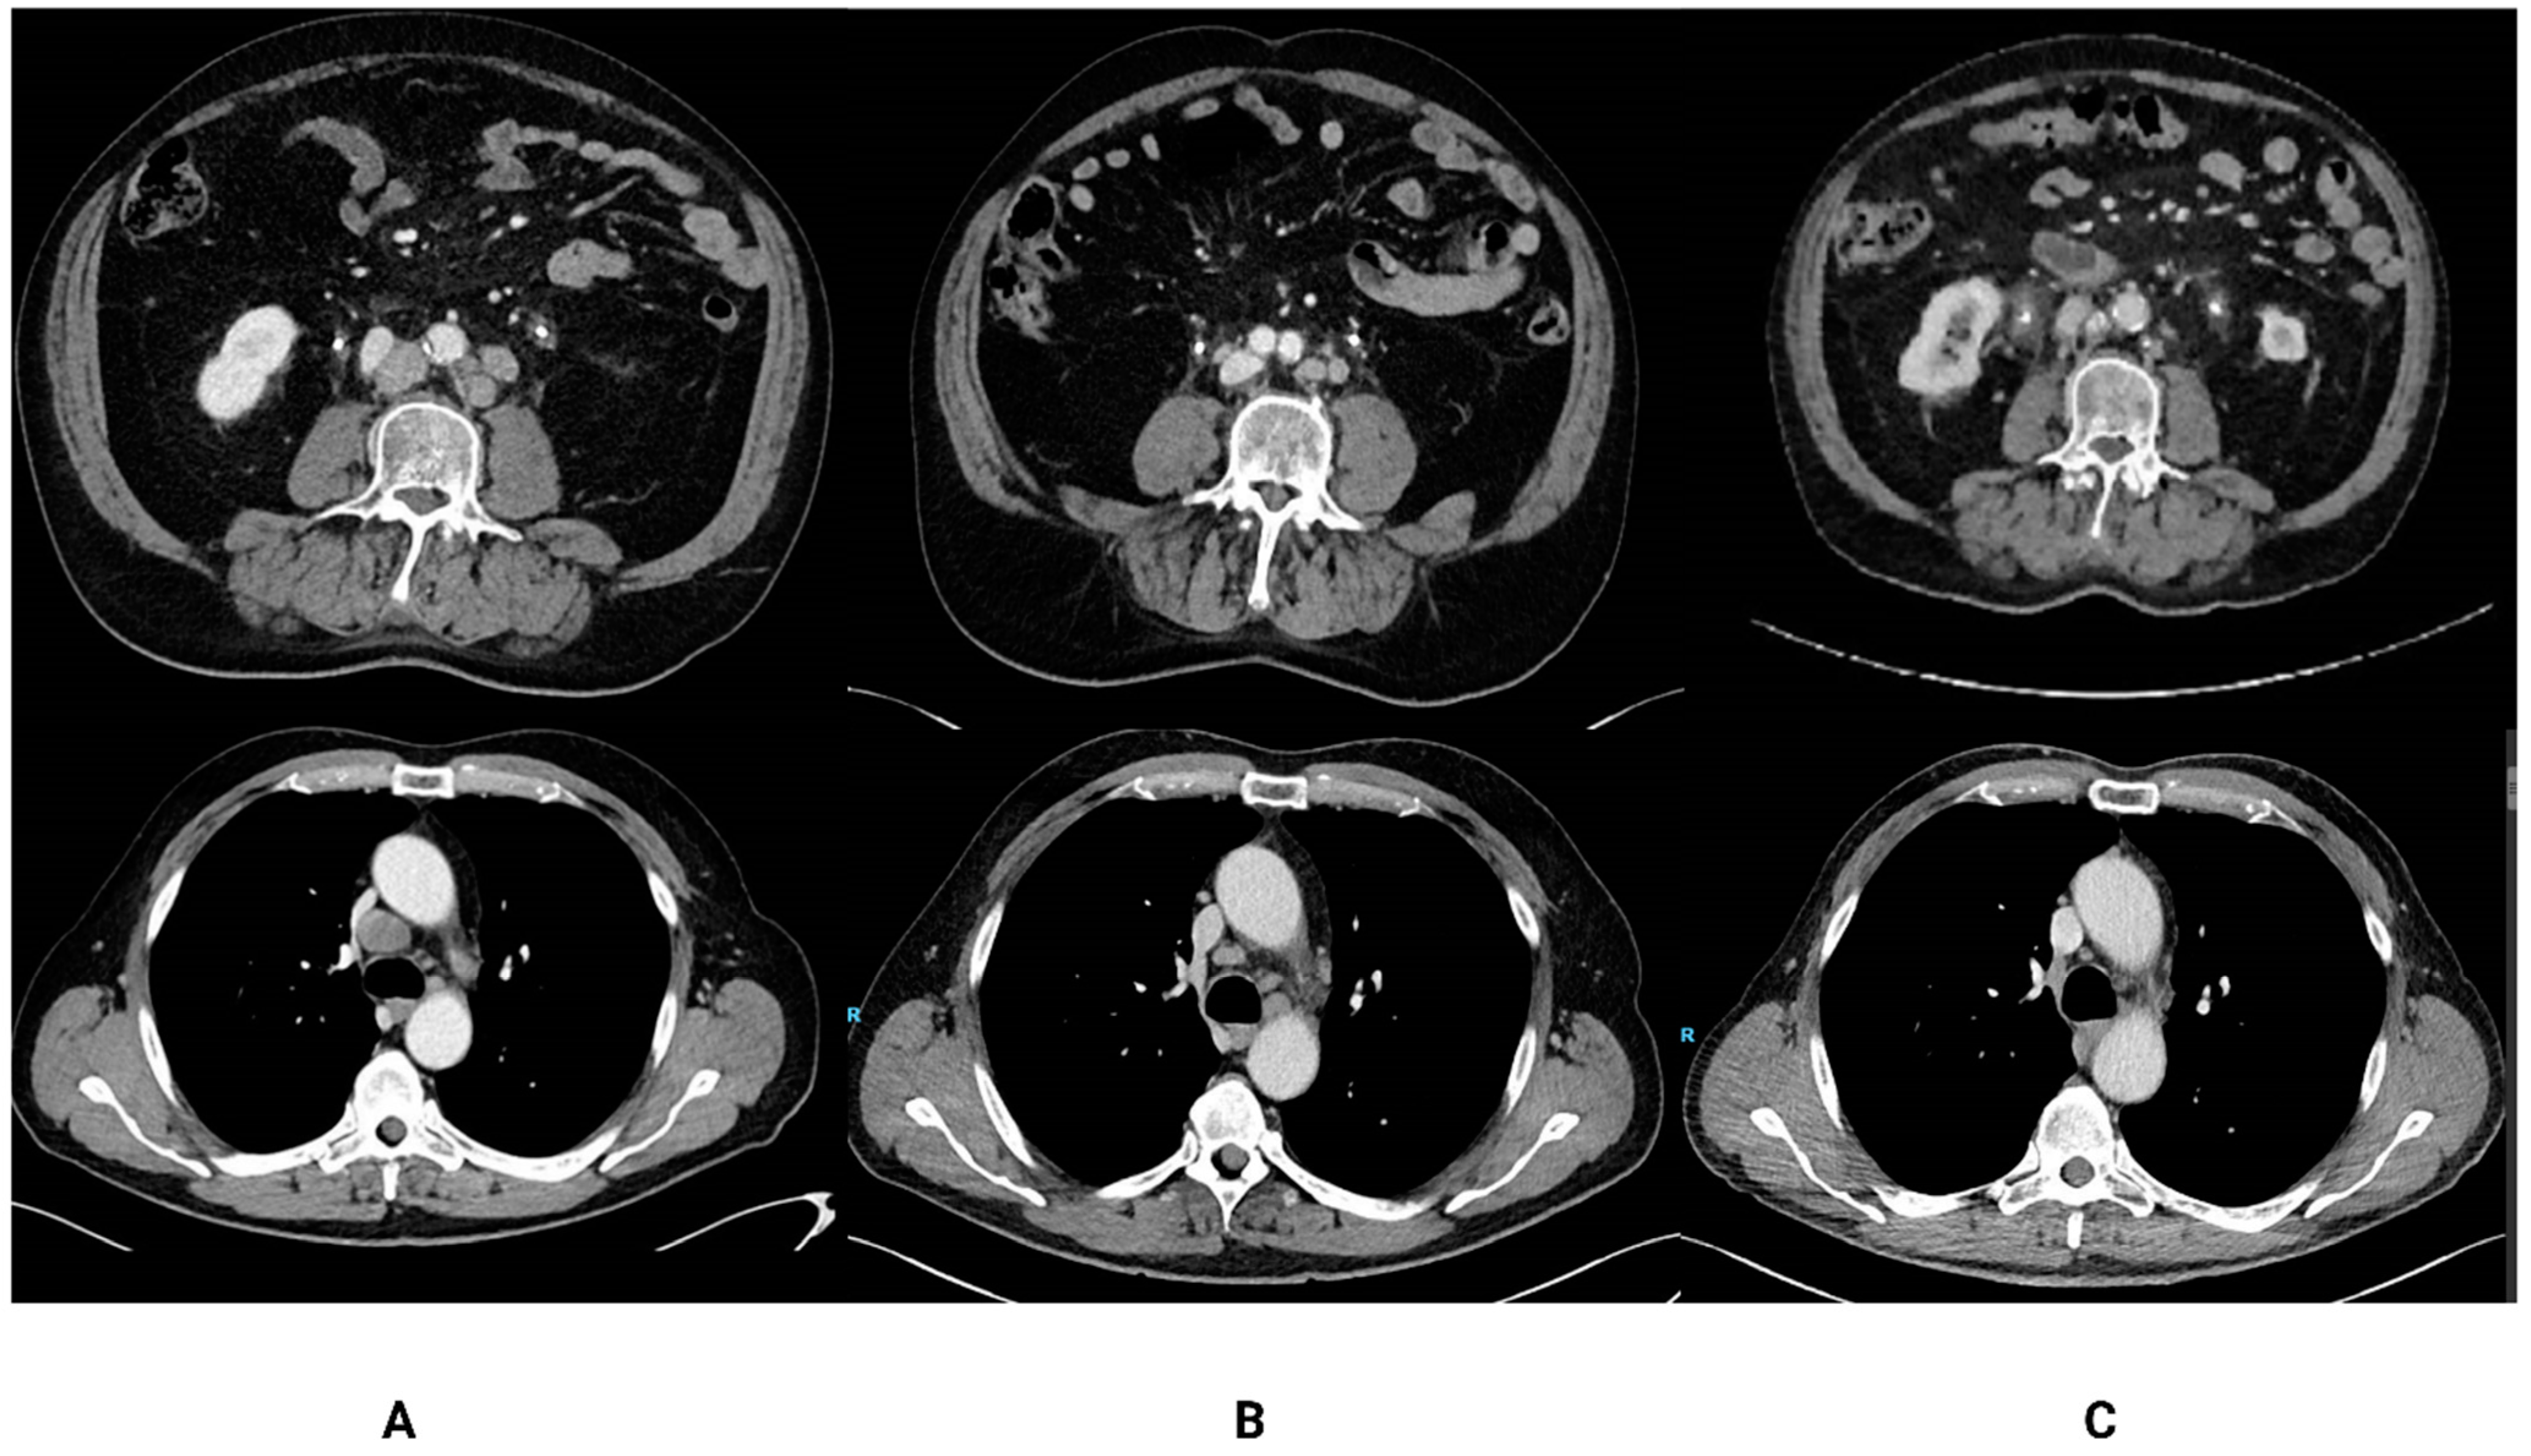

These seven patients had a median treatment duration of 8.5 months, and disease status at the moment of pembrolizumab discontinuation was either SD (n = 1), PR (n = 3) or CR (n = 3). The characteristics of these patients are summarized in Table 1 and Table 2. Five out of seven patients had PD-L1-positive disease (combined positive score ≥ 10), and no patients had visceral metastases. At the time of data cut-off (1 July 2020), the median follow-up period was 35 months and five patients (71%) were still alive (Figure 1). One patient was re-treated with pembrolizumab upon progressive disease with ongoing stable disease at data cut-off. One patient was re-treated with stereotactic radiotherapy of the primary tumor followed by pembrolizumab, reaching complete response for the second time. The other two patients were treated with docetaxel (only one cycle) and carboplatin/gemcitabine, respectively, as the next line of treatment. Figure 2 illustrates two out of seven patients treated <12 months and a durable response of disease.

Figure 2. CT-scans of two patients treated <12 months with pembrolizumab at baseline (A), just prior to discontinuation of pembrolizumab (B) and during follow-up 29 and 41 months resp. after discontinuation of therapy (C). The upper row illustrates scans of a patient with non-visceral metastatic disease with discontinuation of treatment with pembrolizumab after eight cycles due to immune-mediated colitis. He developed progressive disease 34 months after discontinuation. The lower row illustrates scans of a patient who also had non-visceral metastatic disease, whose treatment with pembrolizumab was interrupted after seven cycles due to arthritis; this patient has ongoing response up until today (38 months after discontinuation of pembrolizumab).